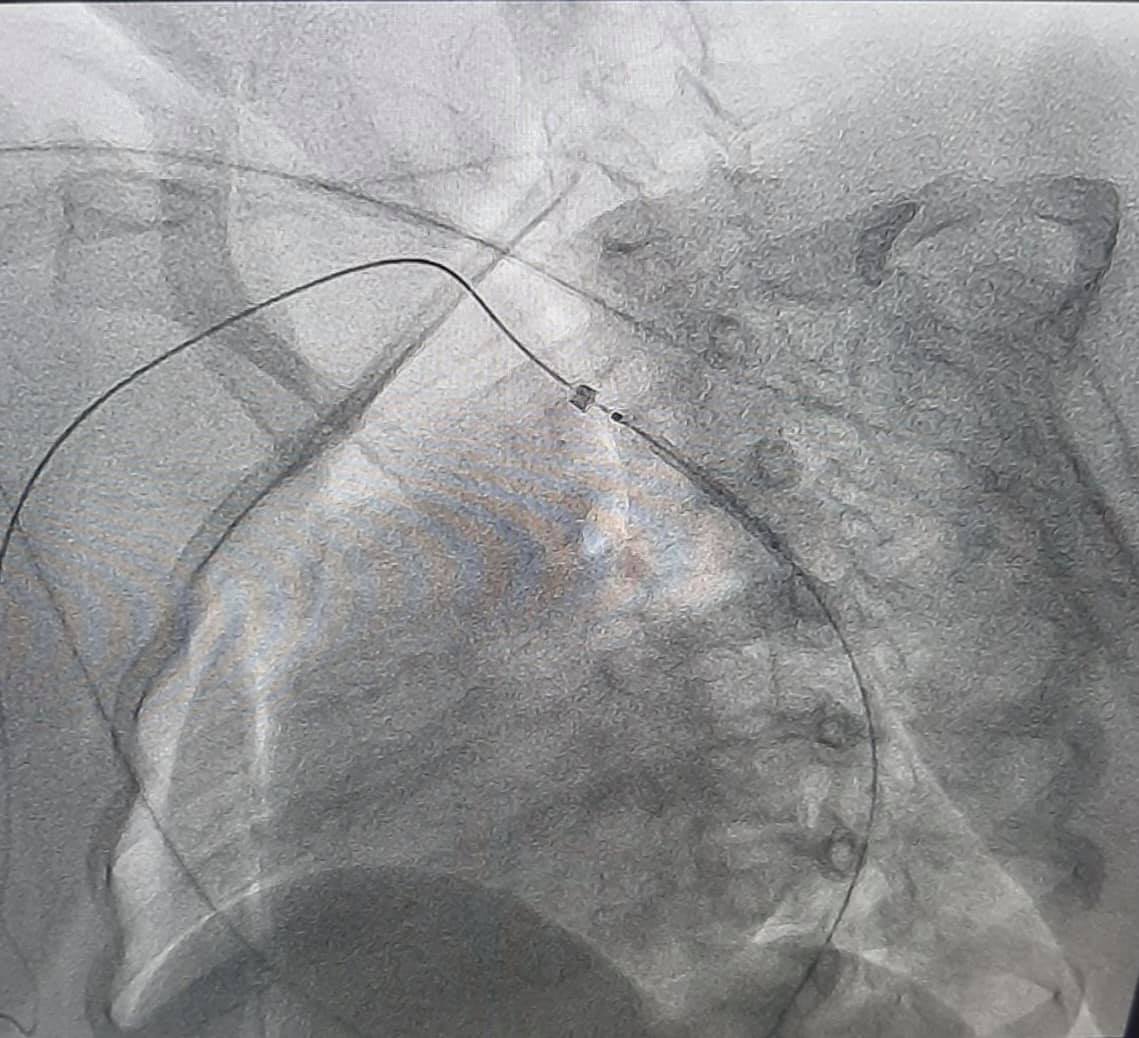

При обследовании у девочки обнаружили врожденный порок сердца - коарктацию аорты. Это состояние, при котором сужен просвет аорты, вследствие чего развивается повышенное давление в верхней половине тела.

Современные технологии на основе результатов обследования помогли провести виртуальную реконструкцию анатомии аорты и ее ветвей. Это помогло медикам выбрать наиболее современную и малотравматическую тактику дальнейшего лечения.

Врожденный порок сосуда был ликвидирован с помощью малоинвазивной эндоваскулярной процедуры - установление стента в просвет сосуда.

"Результат лечения не замедлил и сразу после оперативного вмешательства у ребенка нормализовалось артериальное давление, а также исчезла разница давления между верхними и нижними конечностями", - сообщили медики.